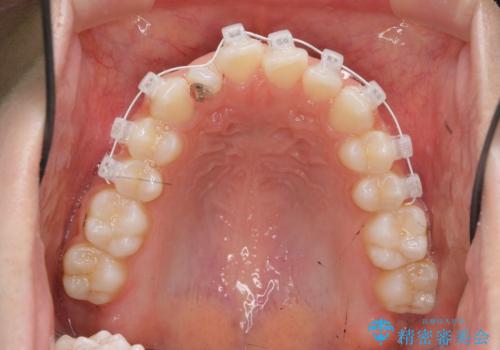

- 矯正装置

- インビザライン

マウスピース矯正インビザラインによる矯正治療を計画しますが、マウスピース矯正で治りにくい歯のねじれを事前にワイヤー矯正でしっかりとなおしておくことで矯正治療期間の短縮できるような治療計画を立てます。

マウスピース矯正を始める前にワイヤー部分矯正を行ったことで改善のしにくい歯のねじれをしっかりと治すことができました。